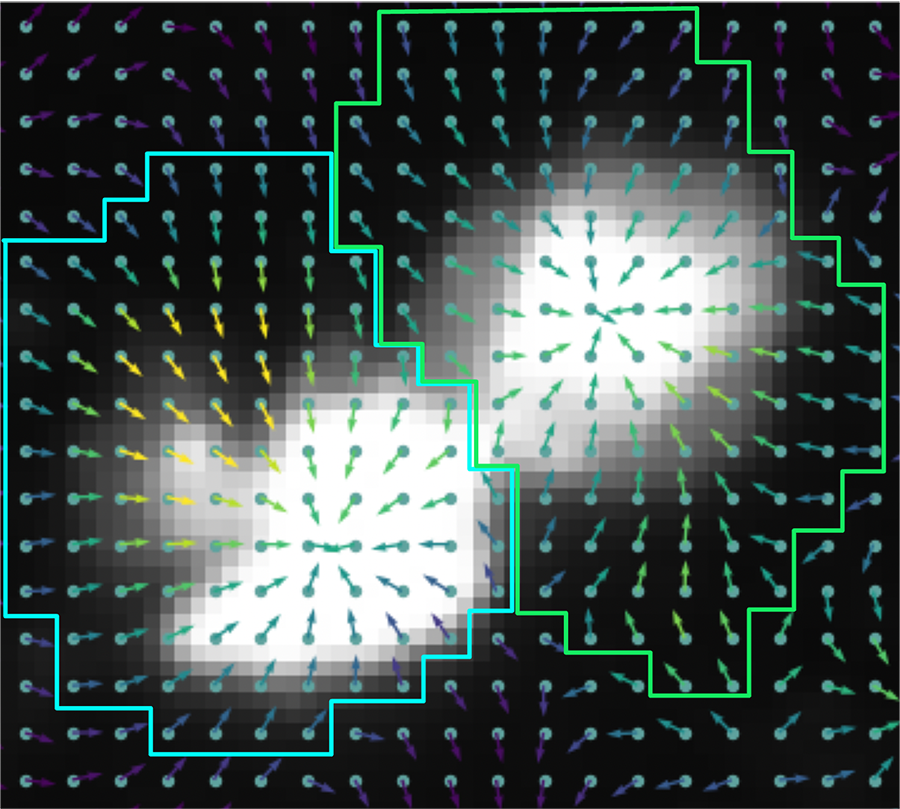

The CMU research focuses on more recent technologies that produce images at a much closer scale, allowing for subcellular resolution (or multiple measurements per cell). While these techniques solve the resolution issue, they present new challenges because the resulting images are so close-up that rather than capturing 15 to 50 cells per image, they capture only a few genes. This reversal of the previous problem creates difficulties in identifying the individual components and determining how to group these measurements to learn about specific cells. It also obscures the big picture.

The algorithm developed by the CBD researchers, called subcellular spatial transcriptomics cell segmentation (SCS), harnesses AI and advanced deep neural networks to adaptively identify cells and their constituent parts. SCS uses transformer models, similar to those used by large language models like ChatGPT, to gather information from the area surrounding each measurement. Just as ChatGPT uses the entire context of a sentence or paragraph for word completion, the SCS method fills in missing information for a specific measurement by incorporating information from the cells around it.

When applied to images of brain and liver samples with hundreds of thousands of cells, SCS accurately identified the exact location and type of each cell. SCS also identified several cells missed by current analysis approaches, such as rare and small cells that may play a crucial role in specific diseases or processes, including aging. SCS also provided information on location of molecules within cells, greatly improving the resolution at which researchers can study cellular organization.